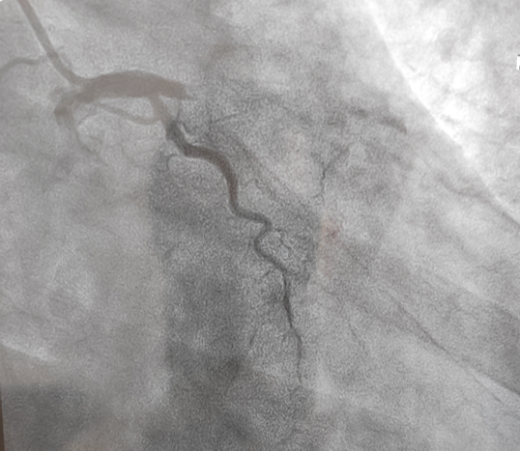

立即啟動綠色通道,急診冠脈造影,結(jié)果顯示前降支近段閉塞,血栓負(fù)荷較重,先后給予血栓抽吸及球囊擴張,血流恢復(fù)正常。李桂武主任和劉興剛主任發(fā)現(xiàn)患者近段狹窄達70%,且中遠(yuǎn)段嚴(yán)重狹窄伴鈣化,此時不適合同期植入支架,如植入支架可能會引發(fā)血管破裂危及生命。當(dāng)務(wù)之急是快速評估出患者是否可以下手術(shù)臺,選擇擇期進行處理,但僅根據(jù)造影結(jié)果又很難做出判斷,李桂武主任和劉興剛主任快速討論研究最后一致決定,給予患者行冠脈OCT檢查,明確病變性質(zhì)。

經(jīng)OCT檢查結(jié)果顯示:前降支中段鈣化,內(nèi)膜光滑,最小管腔面積僅為1.19 mm2。近段斑塊破裂,可見血栓影,最小面積為2.63mm2??蛇x擇先進行抗栓治療,擇期處理冠脈病變。這讓張先生懸著的一顆心終于放下來。